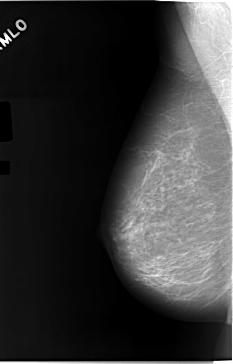

C_0046_1.RIGHT_MLO

LEFT_MLO LINES 5824 PIXELS_PER_LINE 3456 BITS_PER_PIXEL 12 RESOLUTION 50 OVERLAY

RIGHT_MLO LINES 5824 PIXELS_PER_LINE 3720 BITS_PER_PIXEL 12 RESOLUTION 50 NON_OVERLAY